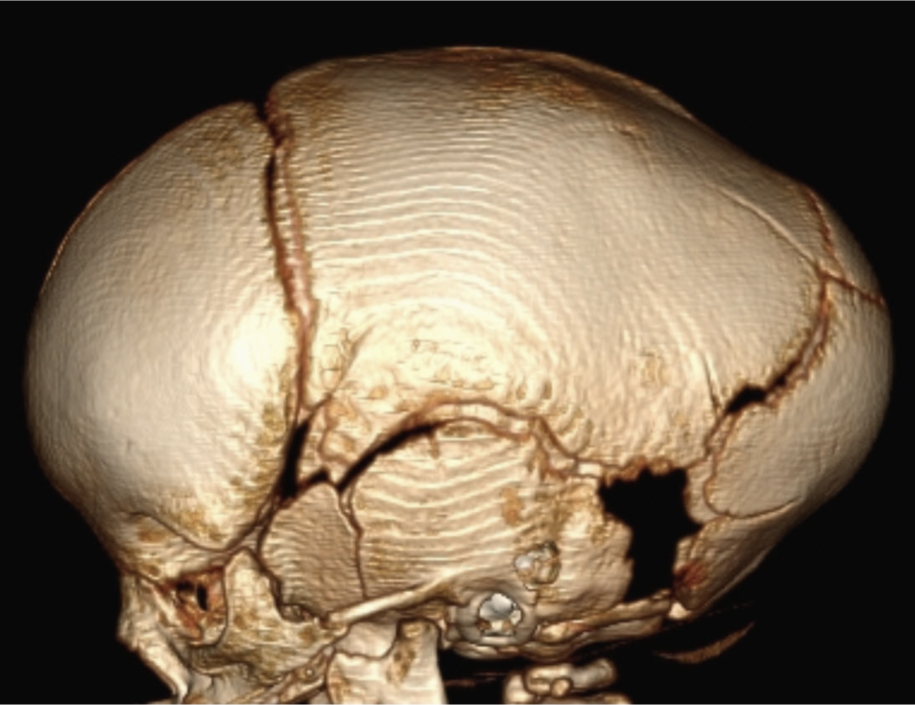

Some sutures normally close in infancy and childhood, such as the metopic suture. Even though this suture normally closes, it can also close prematurely leading to a pointed configuration of the frontal bone (Fig. 1a) and narrowing of the space between the eyes (Fig. 1b).

Craniosynostosis refers to the premature fusion or ossification of the cranial sutures and can occur from genetic etiologies, as well as from some metabolic disorders and mechanical changes, such as in a child with shunted hydrocephalus. With premature closure of a suture or sutures, relatively predictable head shapes and facial distortion occurs. A child with premature fusion of the sagittal suture, the most common type of craniosynostosis, presents with an elongated head shape, as the skull continues to grow along the lambdoid and coronal sutures (Fig. 2).